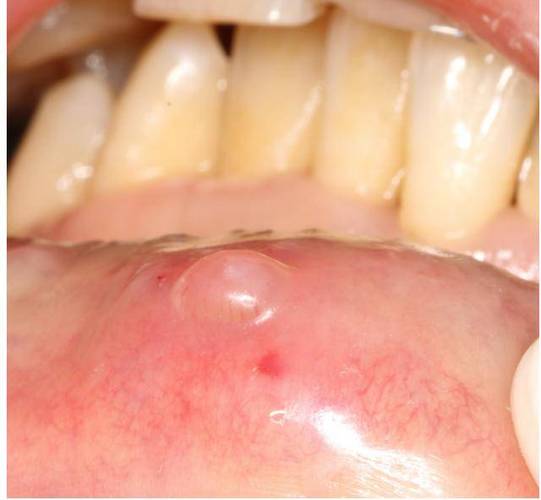

- 口腔黏液腺囊肿: 这是最常见的原因之一,我们的上颚黏膜下分布着许多微小的唾液腺,当腺体的导管被堵塞时,分泌的唾液就会形成一个充满液体的小囊肿,看起来就像透明或半透明的小泡泡,它们通常是柔软的,不痛,但有时可能会因为咀嚼等动作而破裂。